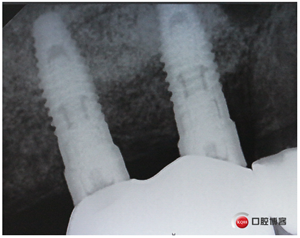

同期植入植體。

說(shuō)書的一張嘴,唱戲的跑斷腿,轉(zhuǎn)眼間半年過(guò)去了,見(jiàn)證時(shí)刻的奇跡到了!

試戴冠,看起來(lái)還不錯(cuò)哈,但我不滿意,大家看看有什么問(wèn)題?看看下頜那幾顆比較明顯。

再看看片子。

問(wèn)題在這里,不給留位置怎么會(huì)有齦乳頭,沒(méi)有間隙怎么清潔?這完全是技工的錯(cuò)吧?算了我自己修整一下吧。